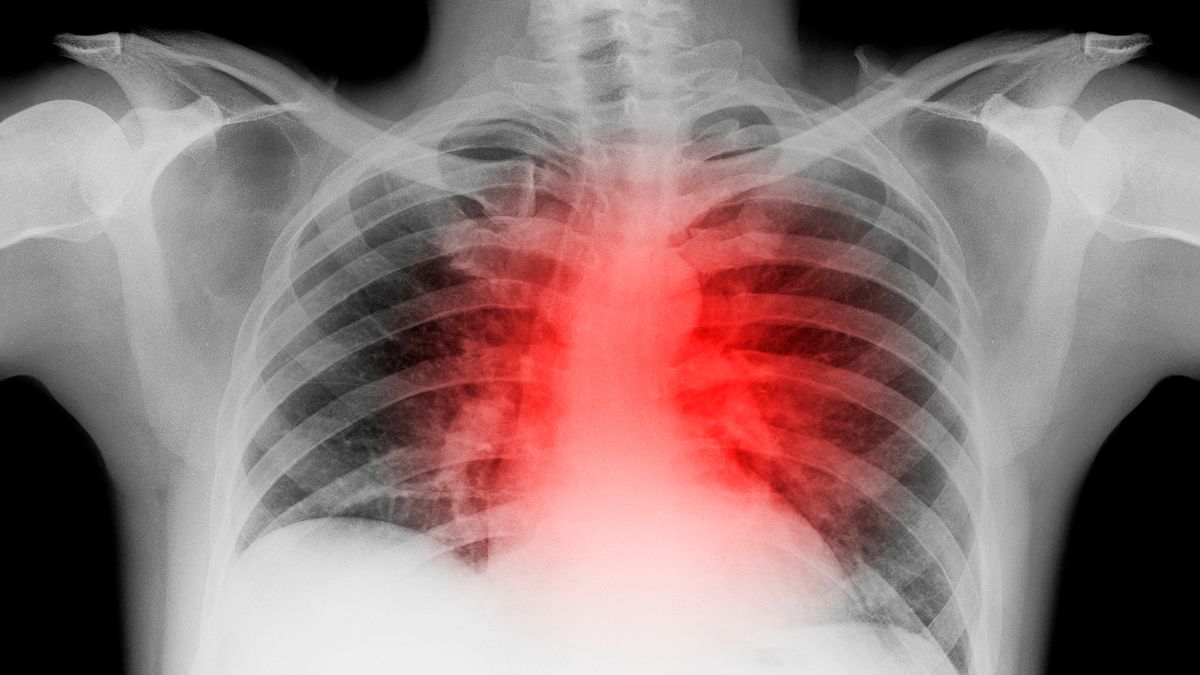

La salud del corazón puede verse afectada, y con efectos duraderos, a consecuencia de la Covid-19, aunque esta puede pasar desapercibida a priori, una vez que el paciente se ha recuperado.

Las secuelas que deja la Covid-19 en el corazón

Esto es lo que se ha descubierto, a raíz de dos estudios realizados en Alemania, publicados el martes en la revista JAMA Cardiology , en los que muestran cómo el virus puede permanecer en el corazón durante meses, incluso sin producir síntomas.

De hecho, de esos 100 pacientes con Covid-19, 78 todavía tenían signos visuales de que el virus tenía un impacto en el corazón. En concreto, sesenta tenían signos de inflamación continua del músculo cardíaco.

«Eso es realmente convincente», ha declarado a NBC News la Dra. Clyde Yancy, jefa de cardiología en el departamento de medicina de Northwestern Medicine en Chicago. «Indica que meses después de la exposición al COVID-19, aún podemos detectar evidencia de un corazón que no es completamente normal».

El problema puede sin embargo no provocar síntomas físicos, aunque evidentemente podría indicar un riesgo de daño cardíaco adicional.

«Una vez que se ha lesionado el músculo cardíaco, existe la posibilidad de una lesión progresiva», escribió Yancy en un editorial que acompaña a los estudios.

El estudio arroja luz a cómo se puede ver de afectado el corazón tras padecer la Covid-19, pero debido a que el virus es nuevo, todavía se desconoce cuáles son los auténticos riesgos cardiovasculares que se pueden sufrir a largo plazo.

Según los autores del estudio, ninguna condición preexistente habría explicado el daño, y solo un tercio de los participantes había sido hospitalizado con Covid-19. El resto había podido permanecer en casa durante el curso de su enfermedad, de modo que a pesar de sentirse relativamente bien o no tener apenas síntomas, es evidente que le han quedado secuelas en el corazón.